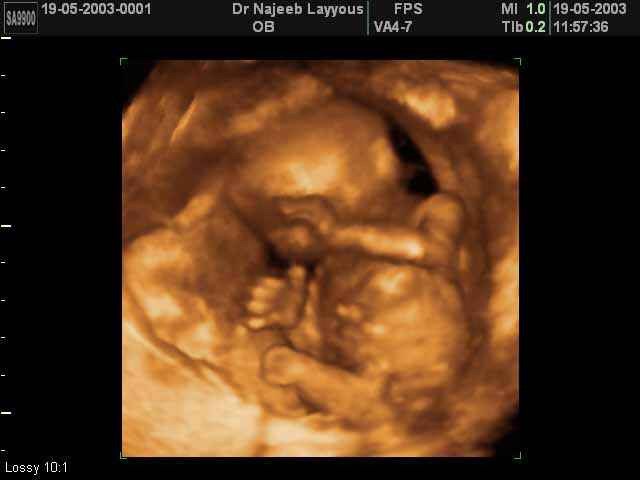

- تصرفات الجنين داخل الرحم

- صور لتصرفات الجنين داخل الرحم

صور لتصرفات الجنين داخل الرحم بجهاز الالتراساوند ثلاثي الأبعاد | الدكتور نجيب ليوس